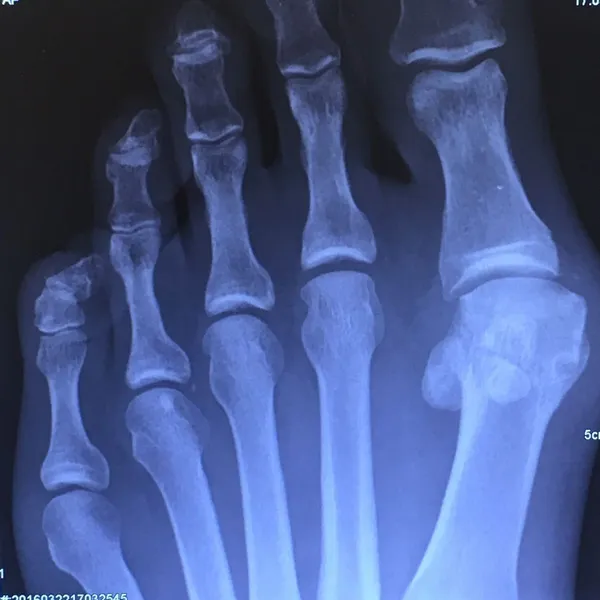

Before and immediately postop S/P bunionectomy

In the x-ray image below is a Hallux Valgus or what is more commonly known as a bunion deformity where the great toe is deviated towards the lesser toes causing abnormal structure which is a result of genetics, abnormal shoegear and abnormal mechanics will cause wearing of the joint and enlargement of the head of the long bone called the first metatarsal.

Post-surgical repair of the same patient bunion deformity with the great toe now in rectus (straight) position with surgically placed screws in the head of the first metatarsal that were used to secure fixation of the cut made across the bone to translate the head of the bone laterally in order to reduce the deformity. The screws will remain in place even after the bone heals.